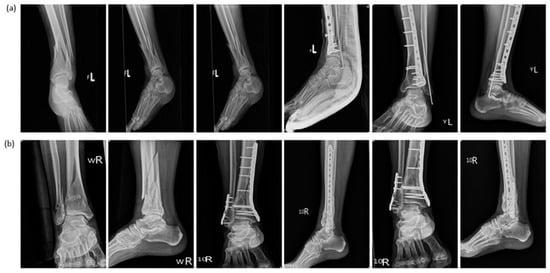

Retrograde Intramedullary Kirschner Wire Fixation as an Alternative for Treating Distal Fibular Shaft Fractures Combined with Distal Tibial Pilon Fractures